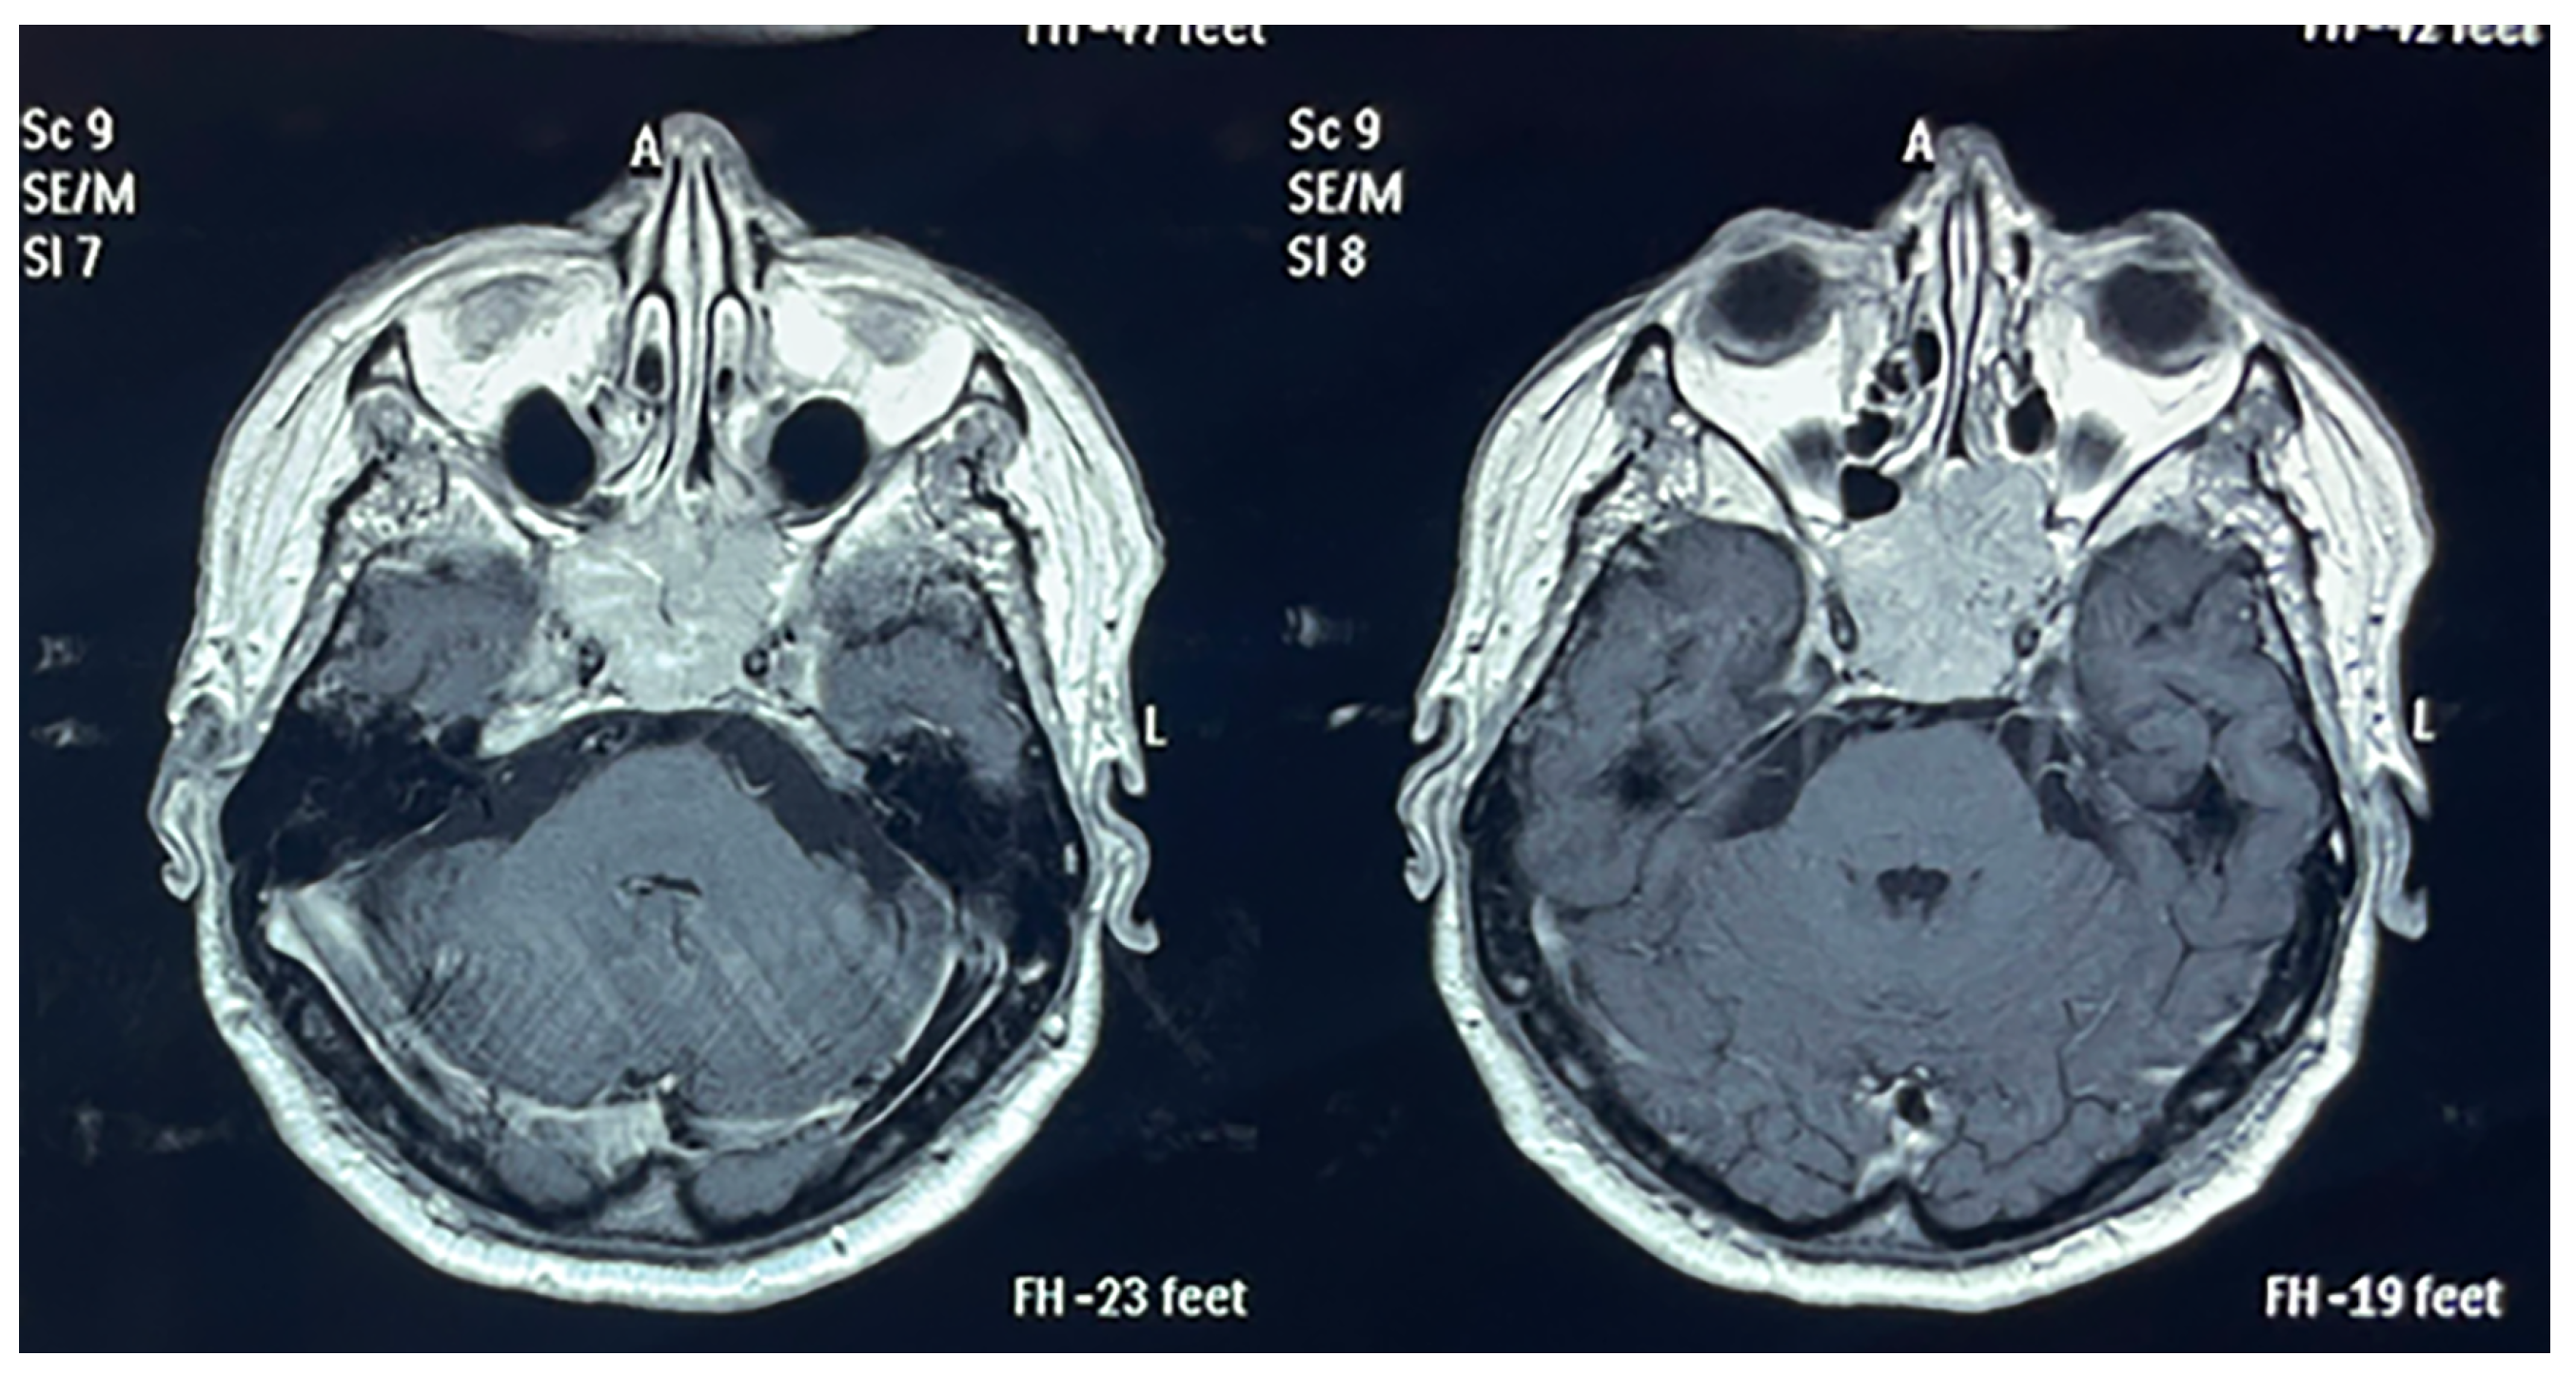

3.3. Neurosurgical Results